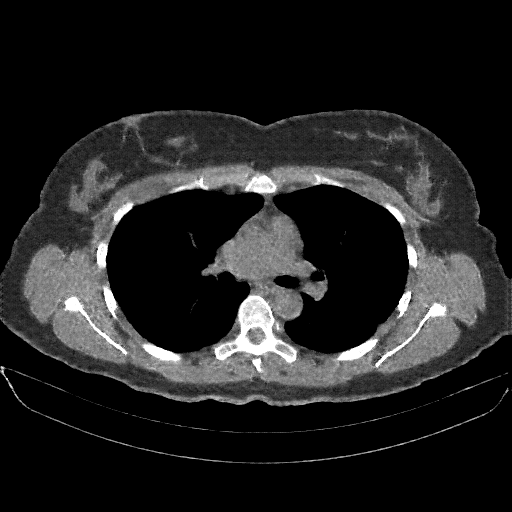

Original VENOUS CT scan

No window - Raw intensity values

Targeted Slice 70 - Lung Window Analysis (Generated vs Real Venous)

0.763

Lung SSIM

85.0

Lung RMSE

36.7

Lung MAE

Average Lung Window Metrics Across All Slices (170 slices) - Generated vs Real Venous

0.767

Lung SSIM (Avg)

89.5

Lung RMSE (Avg)

37.4

Lung MAE (Avg)